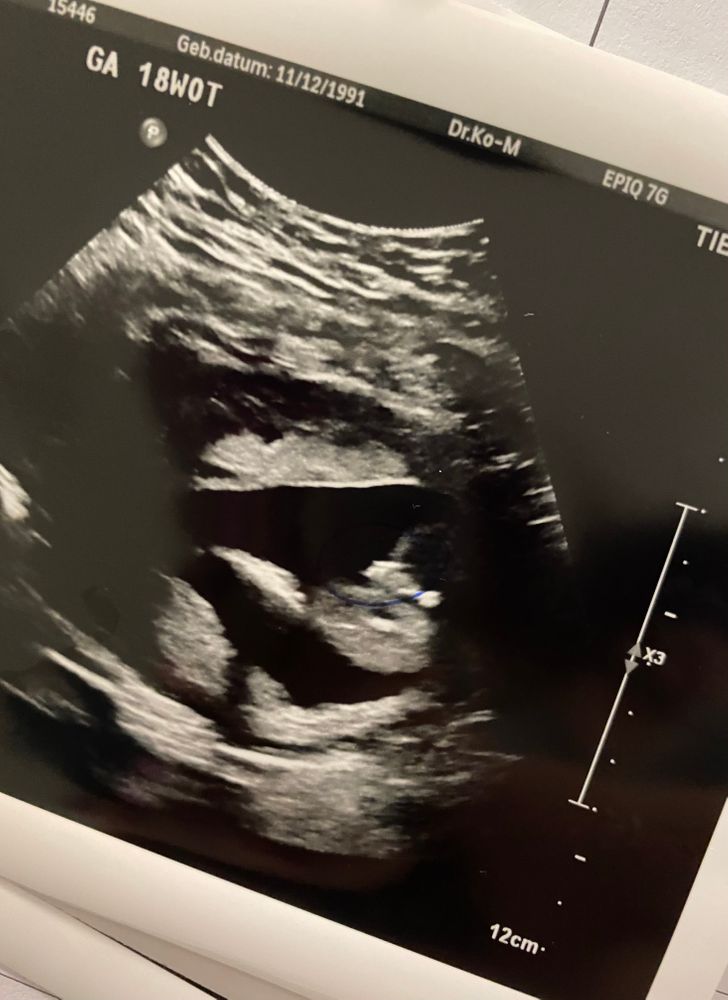

УЗИ, КТГ, доплер18 недель .

Вот на первой фотке вижу пирожок,а на второй бугорок 🤷♀️ Это обе фотки между ножек.

Оля (я скоро мамой стану снова), Девочка под вопросом. Ноги сильно сжаты, поэтому точно не поставила девочку 🤷♀️